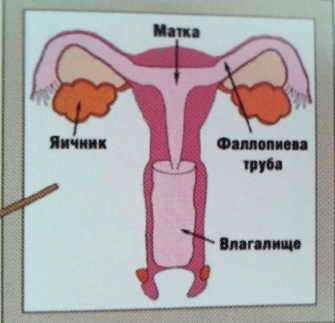

Анатомия женского организма: строение и функции матки

Раздел: Фотопуть к знанию